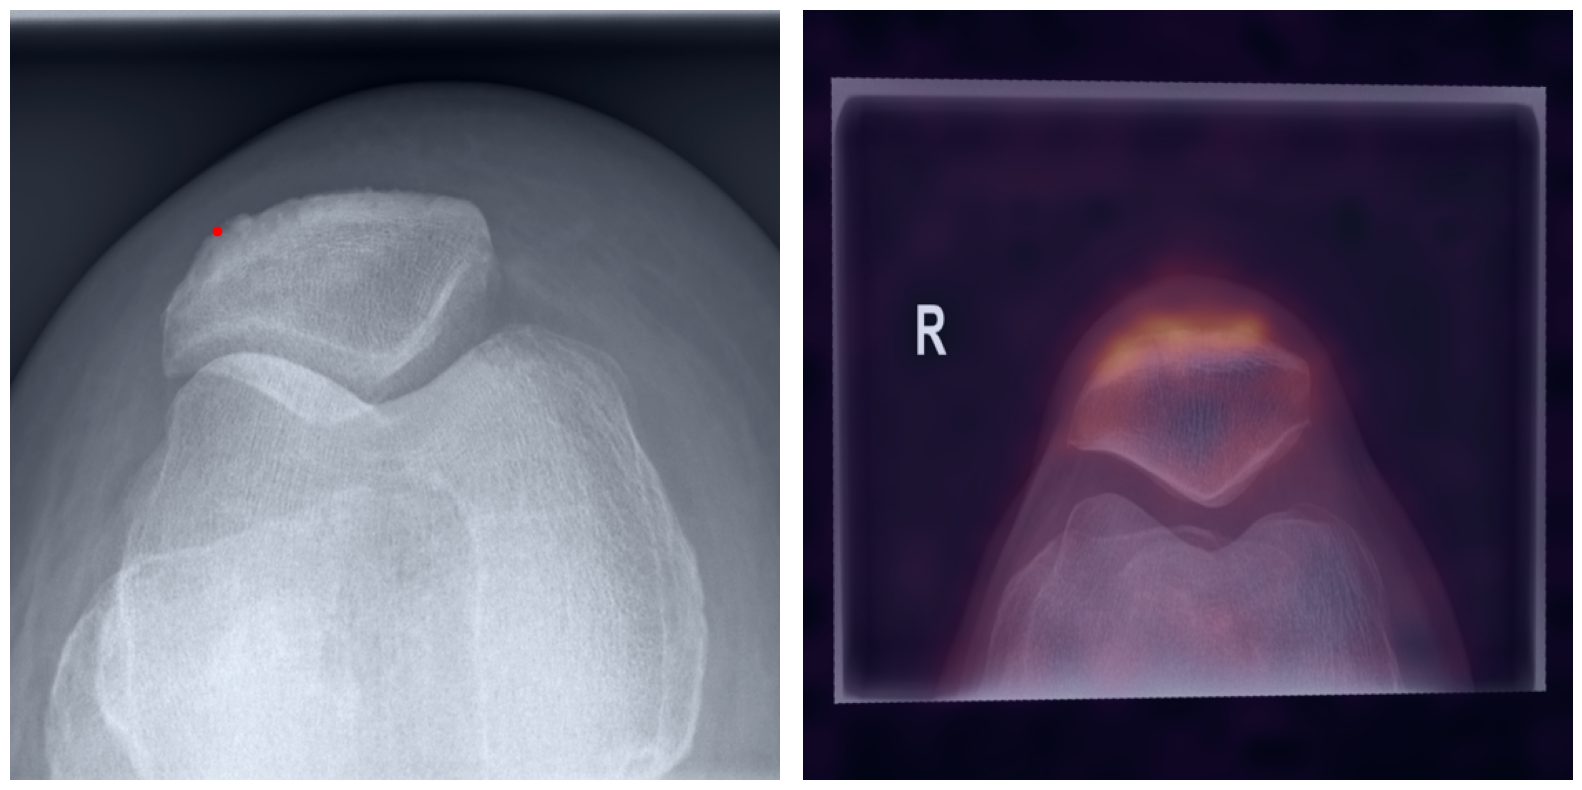

Behind the Curtain: Visualizing the Inner Workings

The process of establishing a dense match between two images relies on abstract feature representations for each position in both the reference and target images. To better understand which information is encoded by the AI, we examined the feature similarities between a specific position within the reference image and the entire target image. Our findings show that the AI captures both semantic and texture features. The matching process utilizes this encoded information, along with precise positional data, to create a reliable mapping between the images.

Hover your mouse over the image to stop automatic transitions.